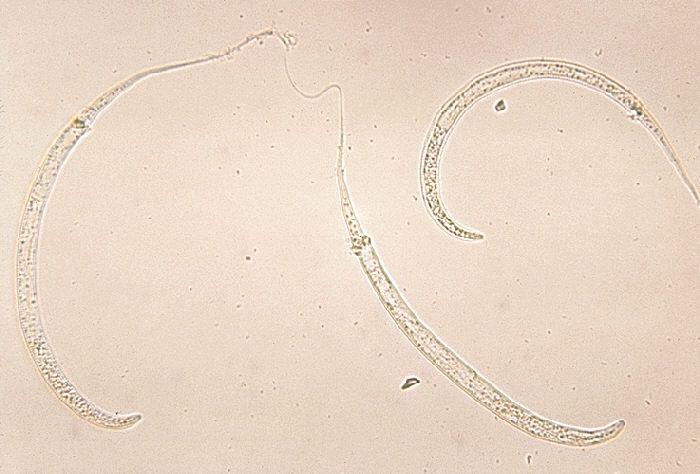

GWD is an infection with the parasite Dracunculus medinensis, spread through contaminated water. In the 1980s, there were more than 3.5 million cases worldwide. Since, GWEP, a collaboration between a number of international and local organizations, has targeted GWD by providing safe sources of drinking water and educating communities about water filtration and other behaviors to minimize disease transmission.